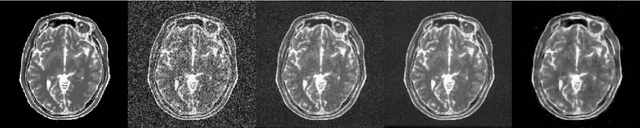

Abstract:In this paper, we propose a method for denoising diffusion-weighted images (DWI) of the brain using a convolutional neural network trained on realistic, synthetic MR data. We compare our results to averaging of repeated scans, a widespread method used in clinics to improve signal-to-noise ratio of MR images. To obtain training data for transfer learning, we model, in a data-driven fashion, the effects of echo-planar imaging (EPI): Nyquist ghosting and ramp sampling. We introduce these effects to the digital phantom of brain anatomy (BrainWeb). Instead of simulating pseudo-random noise with a defined probability distribution, we perform noise scans with a brain-DWI-designed protocol to obtain realistic noise maps. We combine them with the simulated, noise-free EPI images. We also measure the Point Spread Function in a DW image of an AJR-approved geometrical phantom and inter-scan movement in a brain scan of a healthy volunteer. Their influence on image denoising and averaging of repeated images is investigated at different signal-to-noise ratio levels. Denoising performance is evaluated quantitatively using the simulated EPI images and qualitatively in real EPI DWI of the brain. We show that the application of our method allows for a significant reduction in scan time by lowering the number of repeated scans. Visual comparisons made in the acquired brain images indicate that the denoised single-repetition images are less noisy than multi-repetition averaged images. We also analyse the convolutional neural network denoiser and point out the challenges accompanying this denoising method.